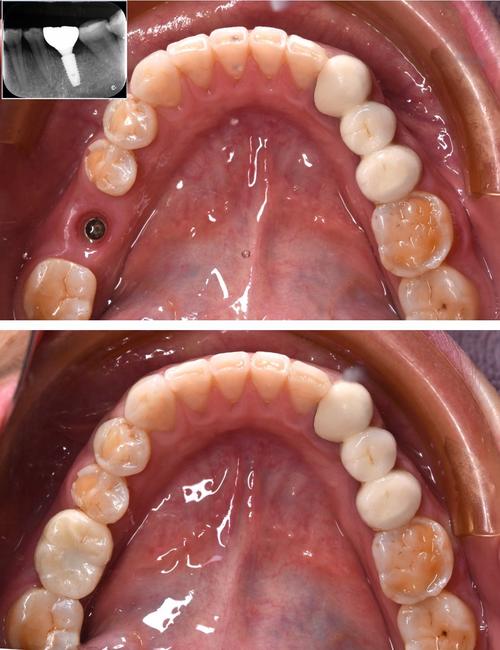

修复阶段的磨牙则针对种植牙的牙冠及咬合关系,种植体植入后3-6个月,当牙槽骨与种植体形成骨结合,即可安装基台和牙冠,此时需通过调磨确保种植牙与邻牙、对颌牙的咬合关系协调,避免早接触或创伤,医生会让患者做正中咬合、前伸及侧方运动,用咬合纸标记接触点,通过图片可清晰看到牙冠上蓝色印记的分布——若印记集中在牙尖某一点,说明存在早接触,需用高速车针精准调磨该区域,直至咬合力分布均匀,调磨后的牙冠图片会显示咬合面呈平滑的窝沟形态,与对颌牙的牙尖窝吻合,避免因咬合异常导致种植体过载松动或颞下颌关节紊乱。

磨牙操作的精准性直接影响种植牙的成功率,因此医生需严格遵循“少量多次”原则,过度磨除骨组织或牙冠会影响长期效果,术前通过影像学图片评估骨条件,术中实时监控磨骨深度,术后通过咬合图片验证调磨效果,是确保磨牙安全有效的关键,患者可通过这些图片直观了解治疗进展,缓解对未知操作的焦虑。